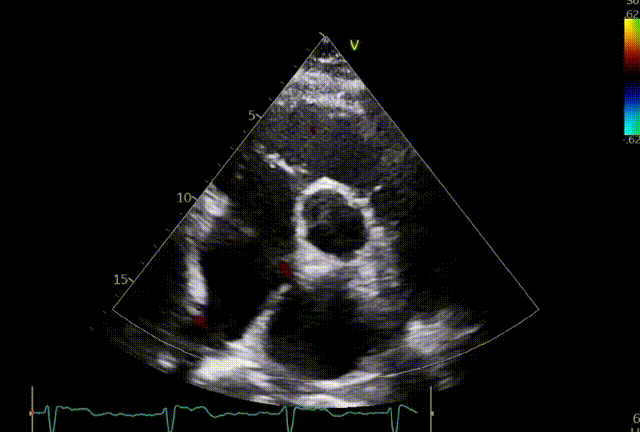

超声评估:1.三尖瓣关闭不全,重度反流(5+);2.反流口位于前隔、中央;3.三尖瓣环扩张(平均瓣环径:43.5mm)。

超声基线

5.关闭夹子后超声评估。

术前

植入第一枚夹子后